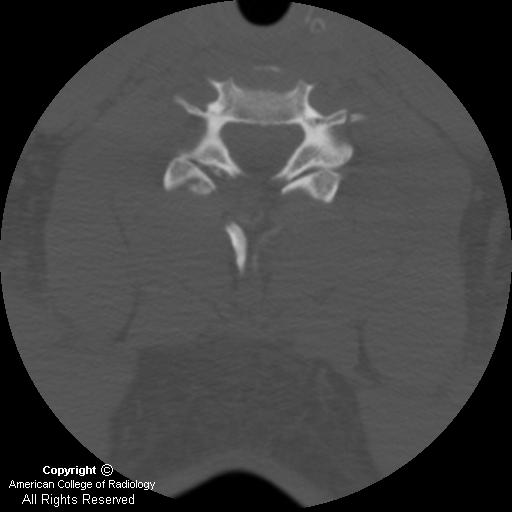

Traumatic unilateral cervical jumped facet: an analysis of failures in a single-institution series of 56 cases Larry T. Khoo, MD1, patients with cervical spine trauma and unilateral jumped facet syndrome who were subsequently treated by anterior cervical discectomy and fusion. ... Access Doc

Severe cervical spine injury with a cal spine, most pronounced in the mid cervical region above the level of distraction injury (arrows). FIGURE 3. CT sagittal reformat of the neck in bone window con - highly suspicious of a jumped facet ... Read More

Advances in Imaging the Traumatized Cervical Spine Corey J. Wallach, translation of C5 on C6, consistent with bilateral jumped facet and cervical instability. Advances in imaging 223. for such missed injuries, has prompted physicians to image ... Access Document

Posterior longitudinal ligament status in cervical spine bilateral facet dislocations or “jumped facets”)[1]. The vertebral body at the dislocated level in anteriorly displaced, and may reside upwards of ... Access Full Source